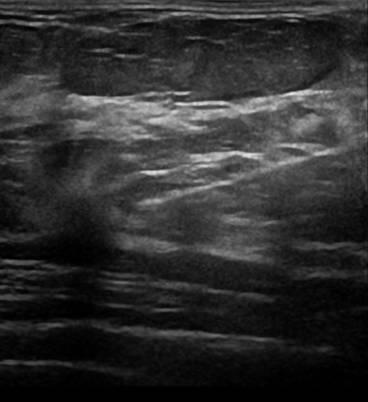

Ung thư vú

» Thông tin: Nữ giới – 62 tuổi.

» Lâm sàng: Kiểm tra sức khỏe.